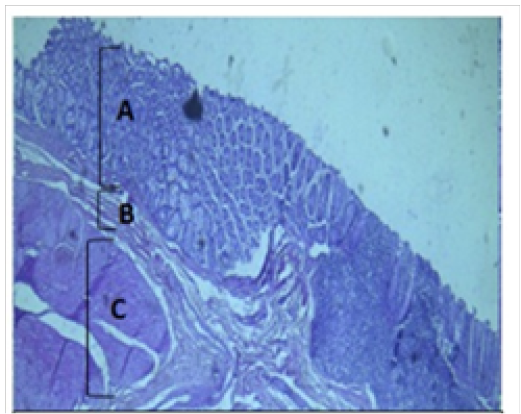

Histological section of cecum Showing:

A- Mucosa B- Submucosa C- Muscularis Externia H&E 40X